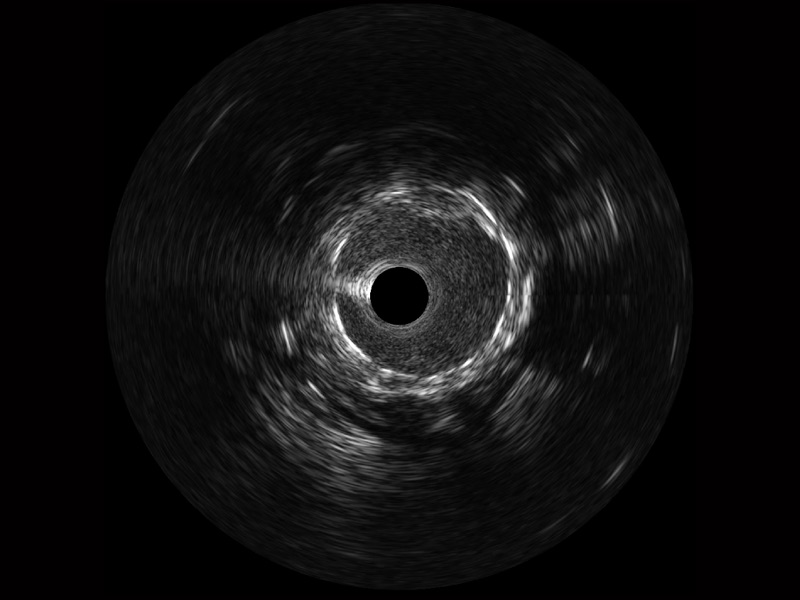

1xBET宽频IVUS图像

对比传统IVUS导管成像,1xBET宽频IVUS图像的近场支架梁显影更细腻,远场中膜外血管仍清晰可辨,兼顾远中近,兼顾分辨力与穿透深度